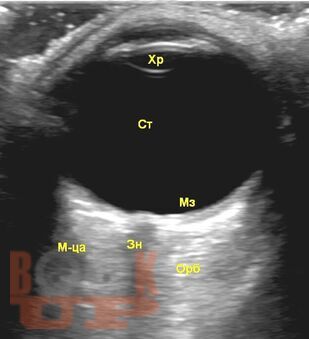

Пособие посвящено ультразвуковой диагностике заболеваний глазного яблока, орбиты. Описана методология ультразвукового исследования глазного яблока и орбиты в В-режиме, режиме допплерографии. Приведены диагностические алгоритмы использования ультразвука в верификации заболеваний глазного яблока, орбиты.

Отдельное внимание уделено клиническим случаям, представлены сонограммы с описанием ультразвуковой картины патологических изменений глазного яблока и орбиты.